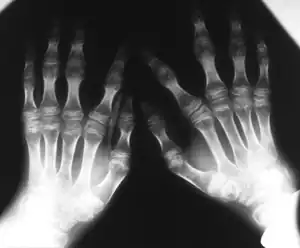

| Kniest dysplasia- Hands demonstrate flattening of metacarpal epiphyses, carpus has a disorganized aspect | |

- Abnormal growth of epiphyses, metaphyses, and diaphysis

- Short tubular bones

- Narrowed joint spaces